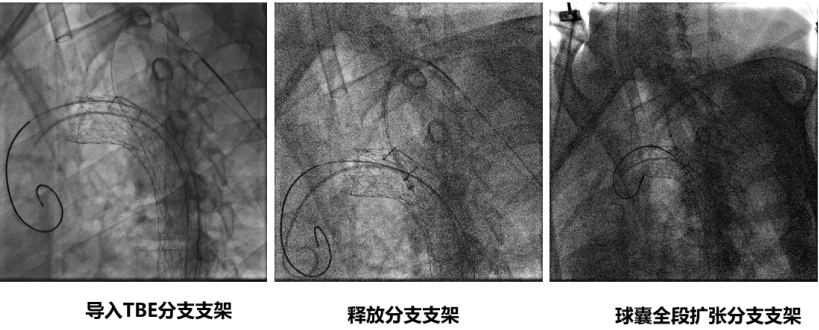

★ 病例3

27岁男性,急性主动脉夹层,破口紧邻左锁骨下动脉。

手术亮点:

TBE支架采用“导丝直出”设计,释放后无需解缠绕,操作简便;

支架柔顺性好,即使成角90°–180°也不打折;

顺应弓部运动,长期通畅率良好,五年随访结果优异。